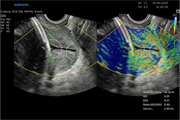

Ultrasound and magnetic resonance imaging features of fetal urogenital anomalies: A pictorial essay Jul 15 2025 - 10:59